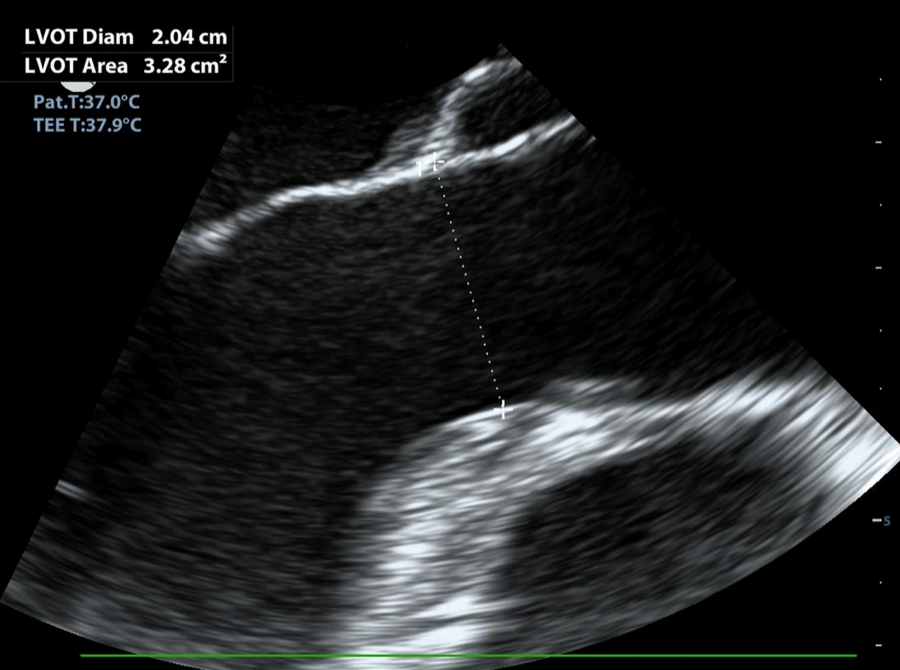

TEE Resus LVOT Measurement Image